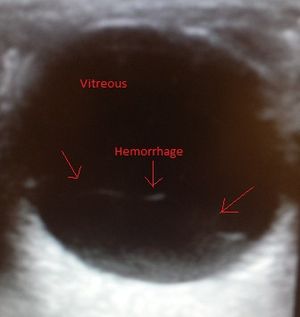

- Ultrasound

- Bright echoes in posterior chamber

- Small dots or mobile lines may represent early, mild hemorrhage

- Look for retinal injury/tears